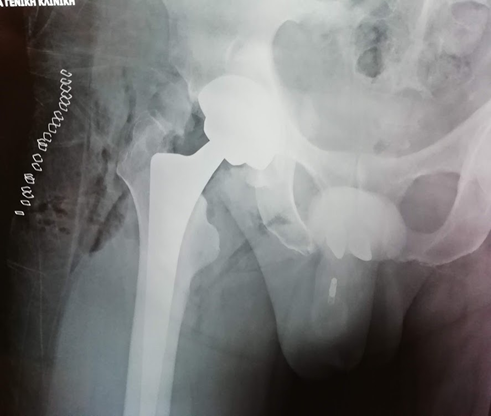

Γυναίκα 30 ετών με υποκεφαλικό κάταγμα τον τελευταίο μήνα της κύησης αντιμετωπίσθηκε αρχικά με ήλωση που απέτυχε